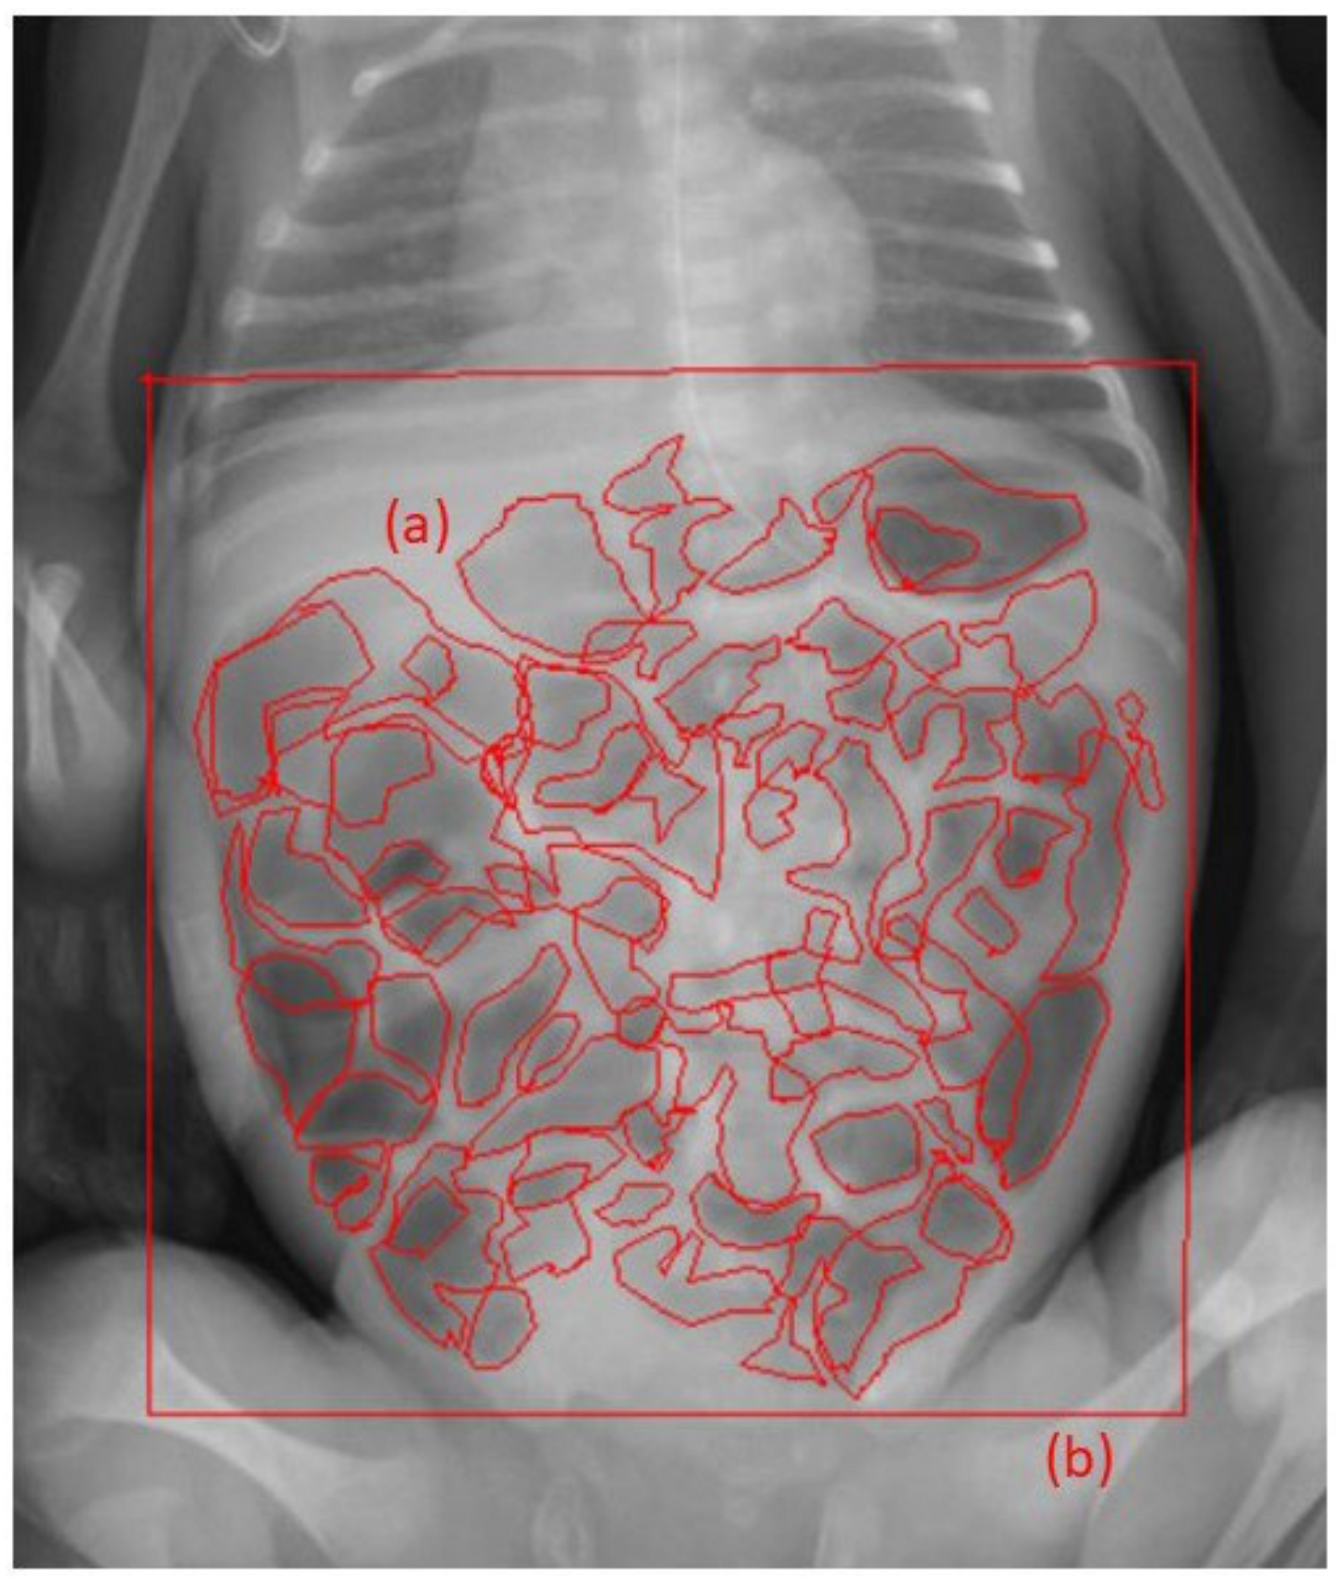

2.5. Evaluation of Abdominal Gas Areas

- Koide, A.; Yamaguchi, T.; Odaka, T.; Koyama, H.; Tsuyuguchi, T.; Kitahara, H.; Ohto, M.; Saisho, H. Quantitative analysis of bowel gas using plain abdominal radiograph in patients with irritable bowel syndrome. Am. J. Gastroenterol. 2000, 95, 1735–1741. [Google Scholar] [CrossRef]

| Gas volume score (GVS) | 0.40 (0.31–0.49) | 0.30 (0.24–0.38) | 0.31 (0.23–0.35) | 0.008 |

| Reduction of GVS, n (%) | - | 22 (92) | 20 (83) | 0.39 |

| ≥20% reduction of GVS, n (%) | - | 11 (46) | 11 (46) | 1.0 |